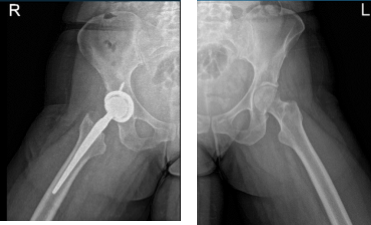

The patient was given status post right total hip arthroplasty using zimmer, said she slept in her side ” by mistake” and felt hip dislocated. She presented an X Ray that showed right total hip arthroplasty, in good alignment. There are no fractures.

Hip Bilateral with pelvis 3 or 4 more view